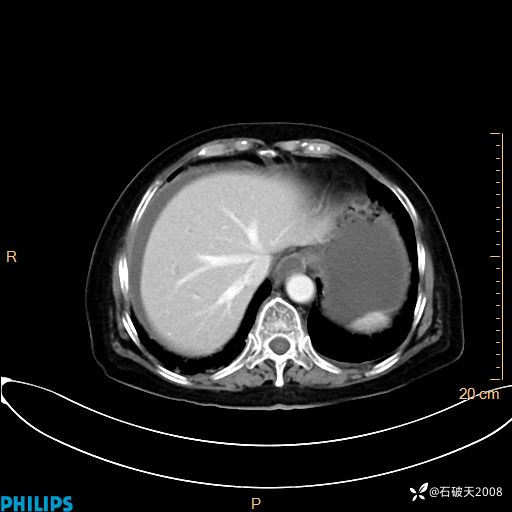

平扫